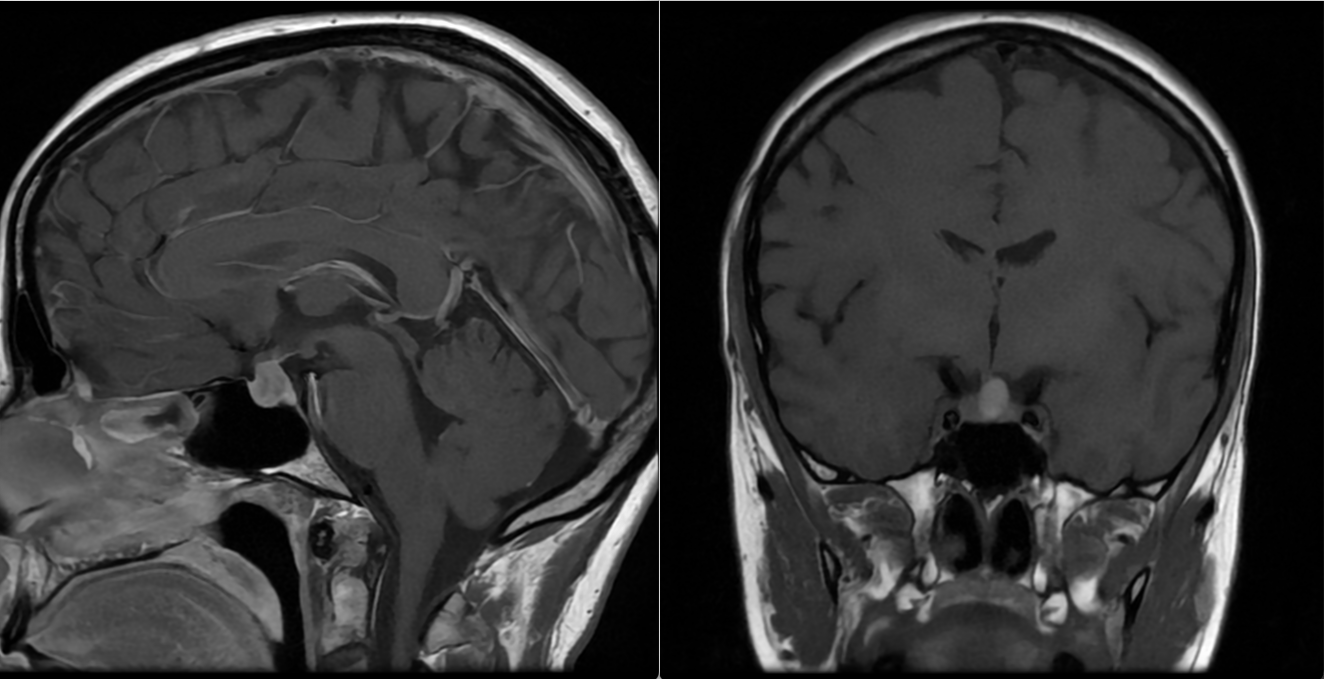

- RMN cerebral cu contrast este metoda de elecție pentru vizualizarea tumorii.

- Macroadenoamele hipofizare apar ca mase tumorale cu priza de contrast localizate la nivelul șeii turcești, eventual cu extensie superioară (supraselară) spre nervii optici sau, mai rar, inferioară, în sinusul sfenoid; de multe ori ele se pot extinde și lateral, în sinusurile cavernoase (structuri vasculare venoase formate în grosimea meningelui care mărginește lateral șaua turcească, prin care trec arterele carotide interne).

Adenoamele hipofizare sunt în marea lor majoritate tumori benigne și, în general, prognosticul este bun, mai ales în cazul microadenoamelor. Prolactinoamele mai ales răspund foarte bine la tratamentul medicamentos, cu remiterea completă a simptomelor și reducerea tumorii. Macroadenoamele compresive sau cele secretoare agresive pot necesita tratamente combinate și monitorizare pe termen lung. Recidiva este posibilă, în special la adenoamele mari sau cele cu invazie locală. Pentru tumorile de mari dimensiuni sau cu invazie în sinusurile cavernoase pot fi necesare operații repetate, seriate, pentru controlul simptomelor. Hipopituitarismul poate apărea ca efect secundar al tratamentului sau al bolii în sine și necesită substituție hormonală pe termen lung.

Monitorizare și urmărire